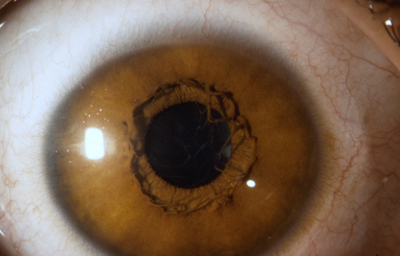

Foto de un Iris humano adulto, con residuos avasculares pigmentados de la membrana pupilar, viniendo del circulo menor. No tiene criptas.

Tomada del archivo fotografico del Dr. CB

Alrededor del 7º mes la vascularización de la porción mesodérmica del Iris, (estroma iridiano) está llegando a su condición definitiva y el circulo vascular menor se reconoce; la túnica vasculosa lentis ya se ha atrofiado en sus porciones posterior y lateral, e inicia atrofia de su porción anterior (membrana pupilar) afectando en primer lugar su zona central; primero en las arcadas finales del centro los vasos se encogen, pierden circulación y quedan formando pequeñas espirales; el ectodermo iridiano con el esfínter ya se ha profundizado, está a nivel de las segundas arcadas vasculares de la membrana pupilar; cuando progresivamente la segunda arcada se atrofia, la membrana queda separada del margen pupilar y toma la apariencia de 2 capas: una anterior (la membrana pupilar) y otra posterior, el margen de la verdadera pupila. Esa grieta o seudoespacio tiene una extensión muy variable; por lo general, solo se ve en el borde de la pupila, pero puede ocurrir que comprometa la capa superficial de vasos periféricamente. Puede ocurrir que el proceso de atrofia no se detenga en la infancia y continue lentamente a lo largo de la vida, hasta que al final toda la hoja vascular anterior se separe del estroma profundo y quede flotando libre en la cámara anterior unida únicamente en la máxima periferia al estroma iridiano (Iridosquisis).

Lo que generalmente se ve, son parches de atrofia localizados periféricamente al margen pupilar, que toman la apariencia de criptas en el estroma.

El modelado final del Iris adulto, tendrá gran cantidad de variaciones dependientes de la cantidad de atrofia de su hoja anterior y de la pigmentación que desarrolle.

El desarrollo del pigmento en el Iris ocurre después del nacimiento y se define después de los 6 meses. Es de anotar que el esculpido del Iris que se aprecia en los adultos con ojos azules o grises, es debido a la visibilidad de las paredes de los vasos; en los iris muy pigmentados el detalle de la estructura queda oculto.